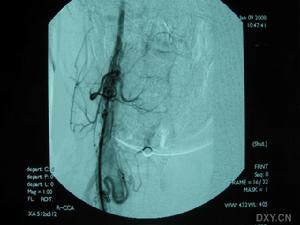

3.腦血管造影有一定的診斷價值71%以上的患者有典型的血管多灶性損害的表現,血管粗細不均,可呈節段性的狹窄或擴張血管阻塞及血管排空延遲等似“臘腸”樣改變,提示腦部血管炎的存在但不能明確是本病的血管炎其他的腦部繼發性血管炎也可有類似的表現有些可因受累的血管太小,腦血管造影可正常

除中樞神經系統症狀外可有發熱、體重下降等全身表現。腦脊液檢查可有細胞數及蛋白的升高,寡克隆區帶陽性。腦活檢可見肉芽腫樣血管炎和/或壞死性血管炎的表現。血管造影可見大腦中小動脈節段性狹窄、擴張及串珠樣改變。1988年Calabrese和Mallek提出了PACNS的診斷標準:①病史和臨床檢查發現原因不明的後天獲得性神經系統損害。②腦血管造影或腦活檢發現有典型血管炎表現。③除外系統性血管炎及其他能引起繼發性中樞神經系統血管炎(血管異常及組織學改變)的各種情況。本例基本皆符合此三條標準。